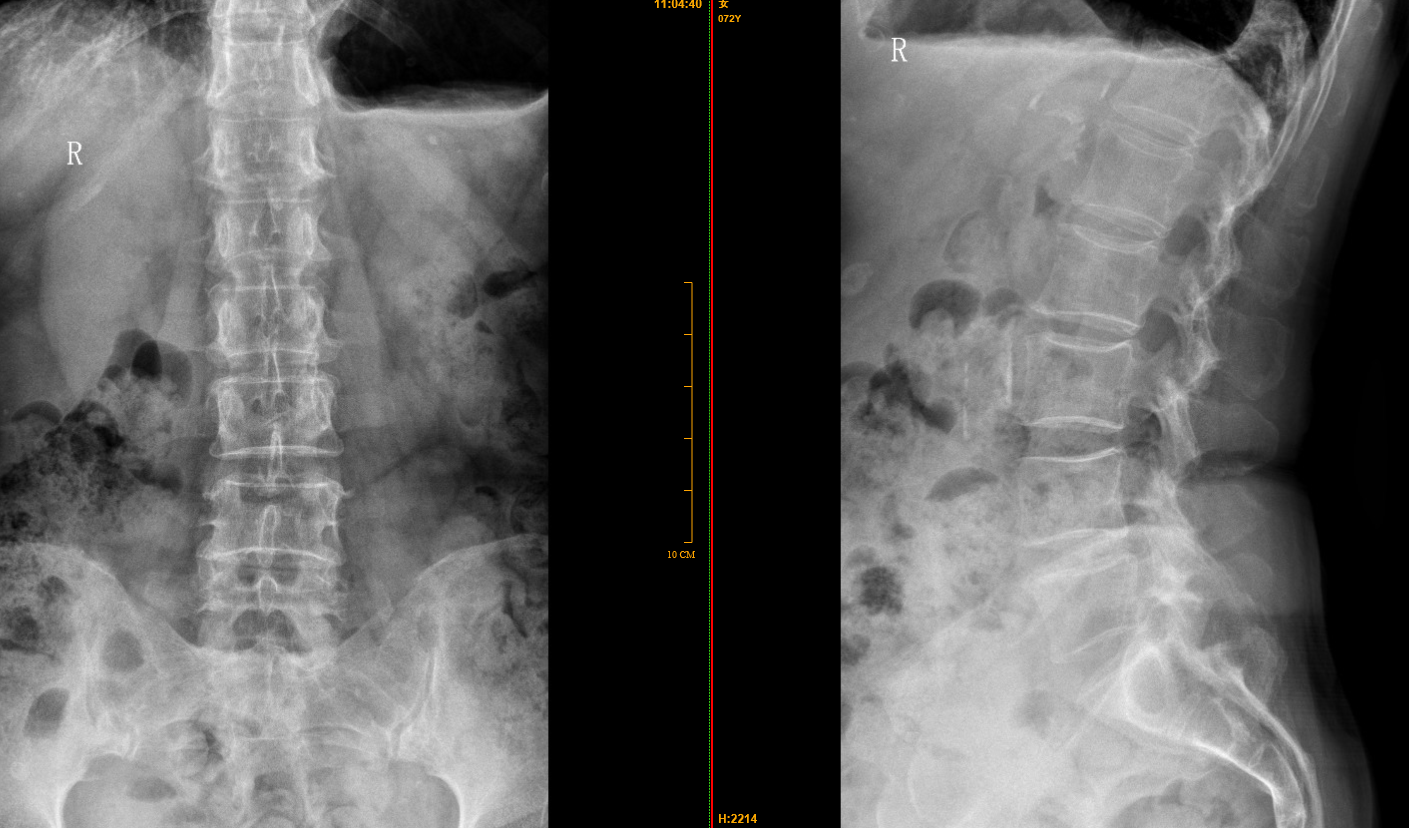

【影像】站立位腰椎正侧位X线片见腰椎轻微向右侧弯,L4-5椎间隙变窄。

【讨论】本案左侧小腿及足外侧感觉异常,影像见L4-5椎间隙变窄,首先考虑腰椎间盘突出所致,然间盘突出相关检查未见阳性体征,排除“腰椎间盘突出症”临床诊断。左侧臀中肌紧张,压痛(+),久压引发小腿及足外侧感觉异常;刃针松解臀中肌后小腿及足外侧异常感觉明显减轻,证实异常皮肤感觉为臀中肌损伤所致。